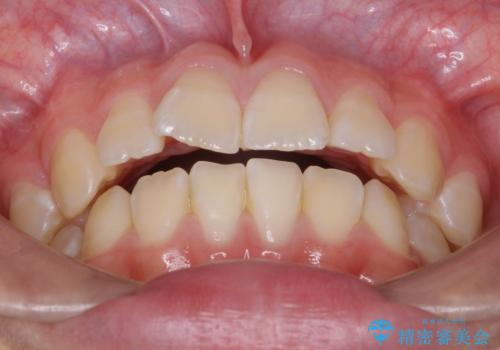

八重歯 歯を抜かずにインビザラインで

- 八重歯を主訴に来院。

抜かずに歯を少し削って入れる方法で並べました。

10代のうちに矯正をしておくと歯の移動は簡単で、歯ぐきも下がりにくいです。

可能なら低年齢のうちに矯正をするのがお勧めです。